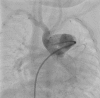

Figure 2.

Aortagram after closure of aortopulmonary window with a muscular ventricular septal defect occluder